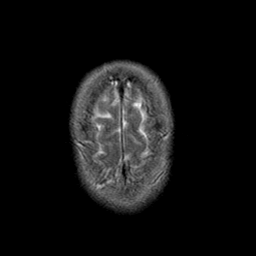

Stroke:T2-weighted MR #1 -- Slice #22

[Home][Help][Clinical] Slice 22